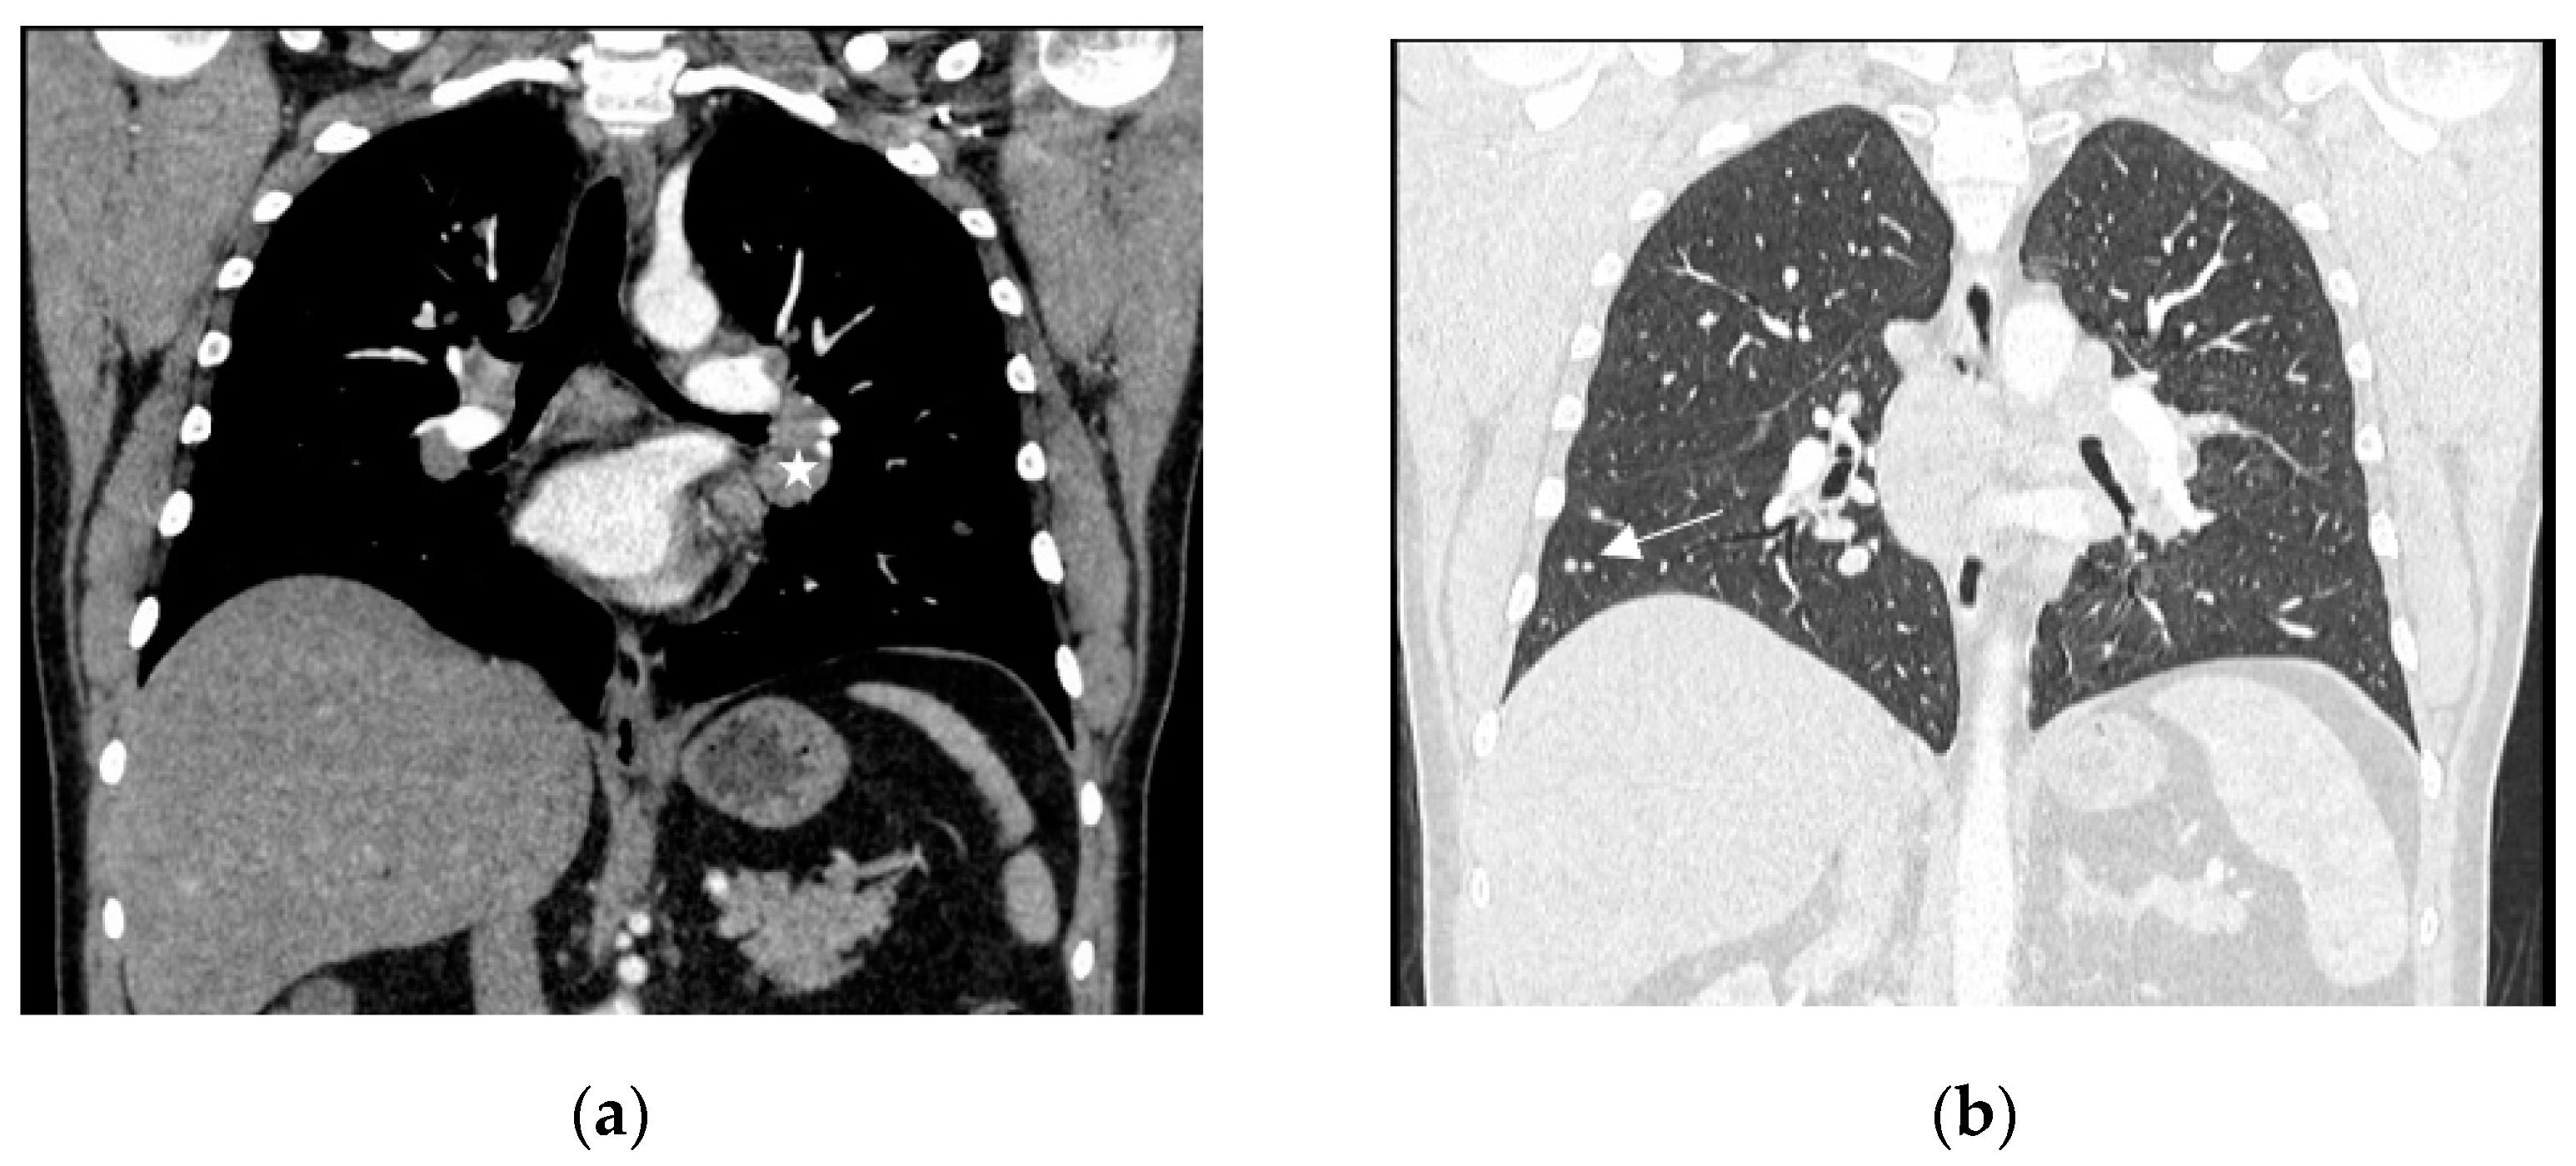

Figure 2.

Computed tomography of the chest, with contrast enhancement, coronal plane, mediastinal window (a), lung window (b). Enlarged mediastinal and hilar lymph nodes ((a)—white asterisk). Small nodules in the right lower lobe ((b)—white arrow).